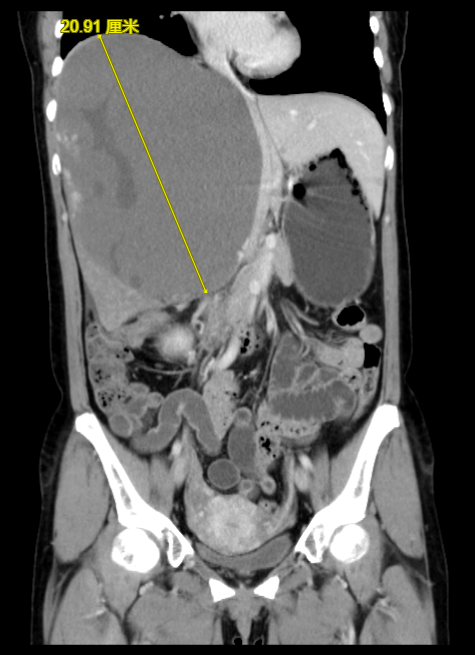

门诊经常会遇到因为体检发现肝血管瘤来咨询的朋友。最近就有一位女士因为右上腹明显胀痛一月,发现肝巨大血管瘤就诊。腹部增强CT可见血管瘤最大径达20cm(图1、2)。考虑肝巨大血管瘤伴有明显不适症状,需要行手术切除,术后患者腹部不适完全缓解。

图1:增强CT可见右肝巨大血管瘤,最大径达20cm